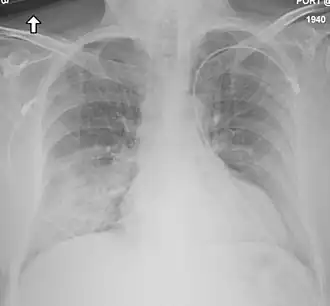

| Radiografia de tórax do primeiro caso norte-americano de coronavírus MERS (MERS-CoV). | |